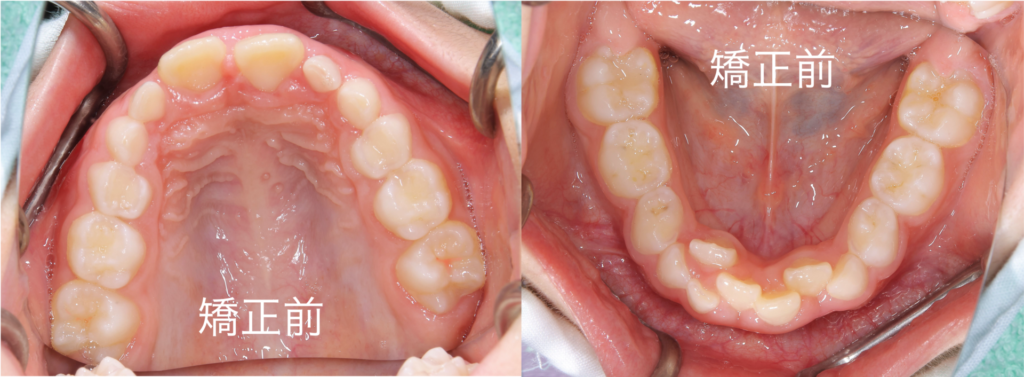

写真のように、特に下顎の前歯にガタつきが生じていました

現状の評価と致しましては、下顎のアーチが狭く歯が並ぶスペースが少ないため、前歯がガタついていると判断いたしました

そのため、下顎の成長を補助し歯列(アーチ)を拡大していくこととしました

今回は患者様の希望もあり、上顎にはクワドヘリックス、下顎にはバイヘリックスという固定式の装置を用いて治療を行っていきました

治療の経過ですが、アーチが広がり歯が整列してきていることが認められます